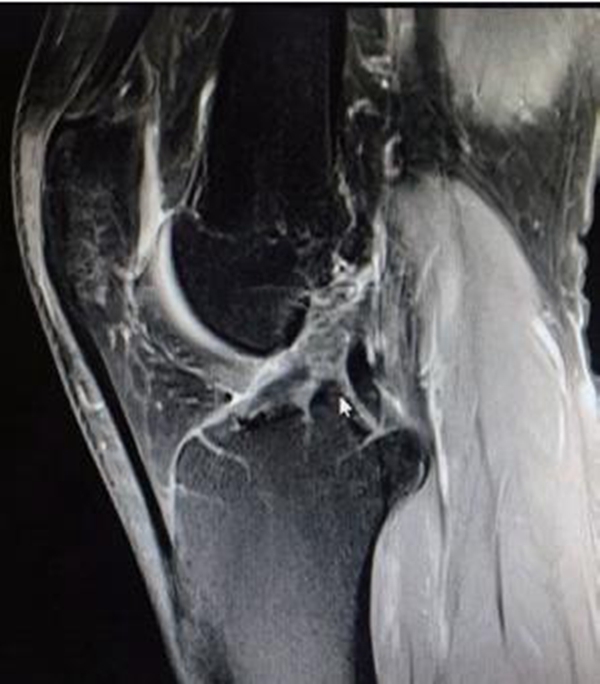

由于ACL的解剖特点,常规MRI扫描方向无法满足精确诊断的需要,因此沿ACL的方向扫描对于诊断有重要的作用。MRI影像上正常的ACL是起自股骨外侧髁内侧面,斜向前内侧走行,止于胫骨髁间隆起前方的一条边缘清晰、光滑、具有张力感的低信号带(图7)。连续性中断是ACL断裂最直观的表现(图8)。

Lee等提出ACL断裂的MRI诊断标准: ①ACL前缘呈不规则波浪状;②T2WI成像中ACL信号内有高信号;③矢状面上ACL信号不连续;④当伴有上述征象之一时,前部呈弓状的PCL可支持ACL撕裂。

图8 ACL断裂MRI影像